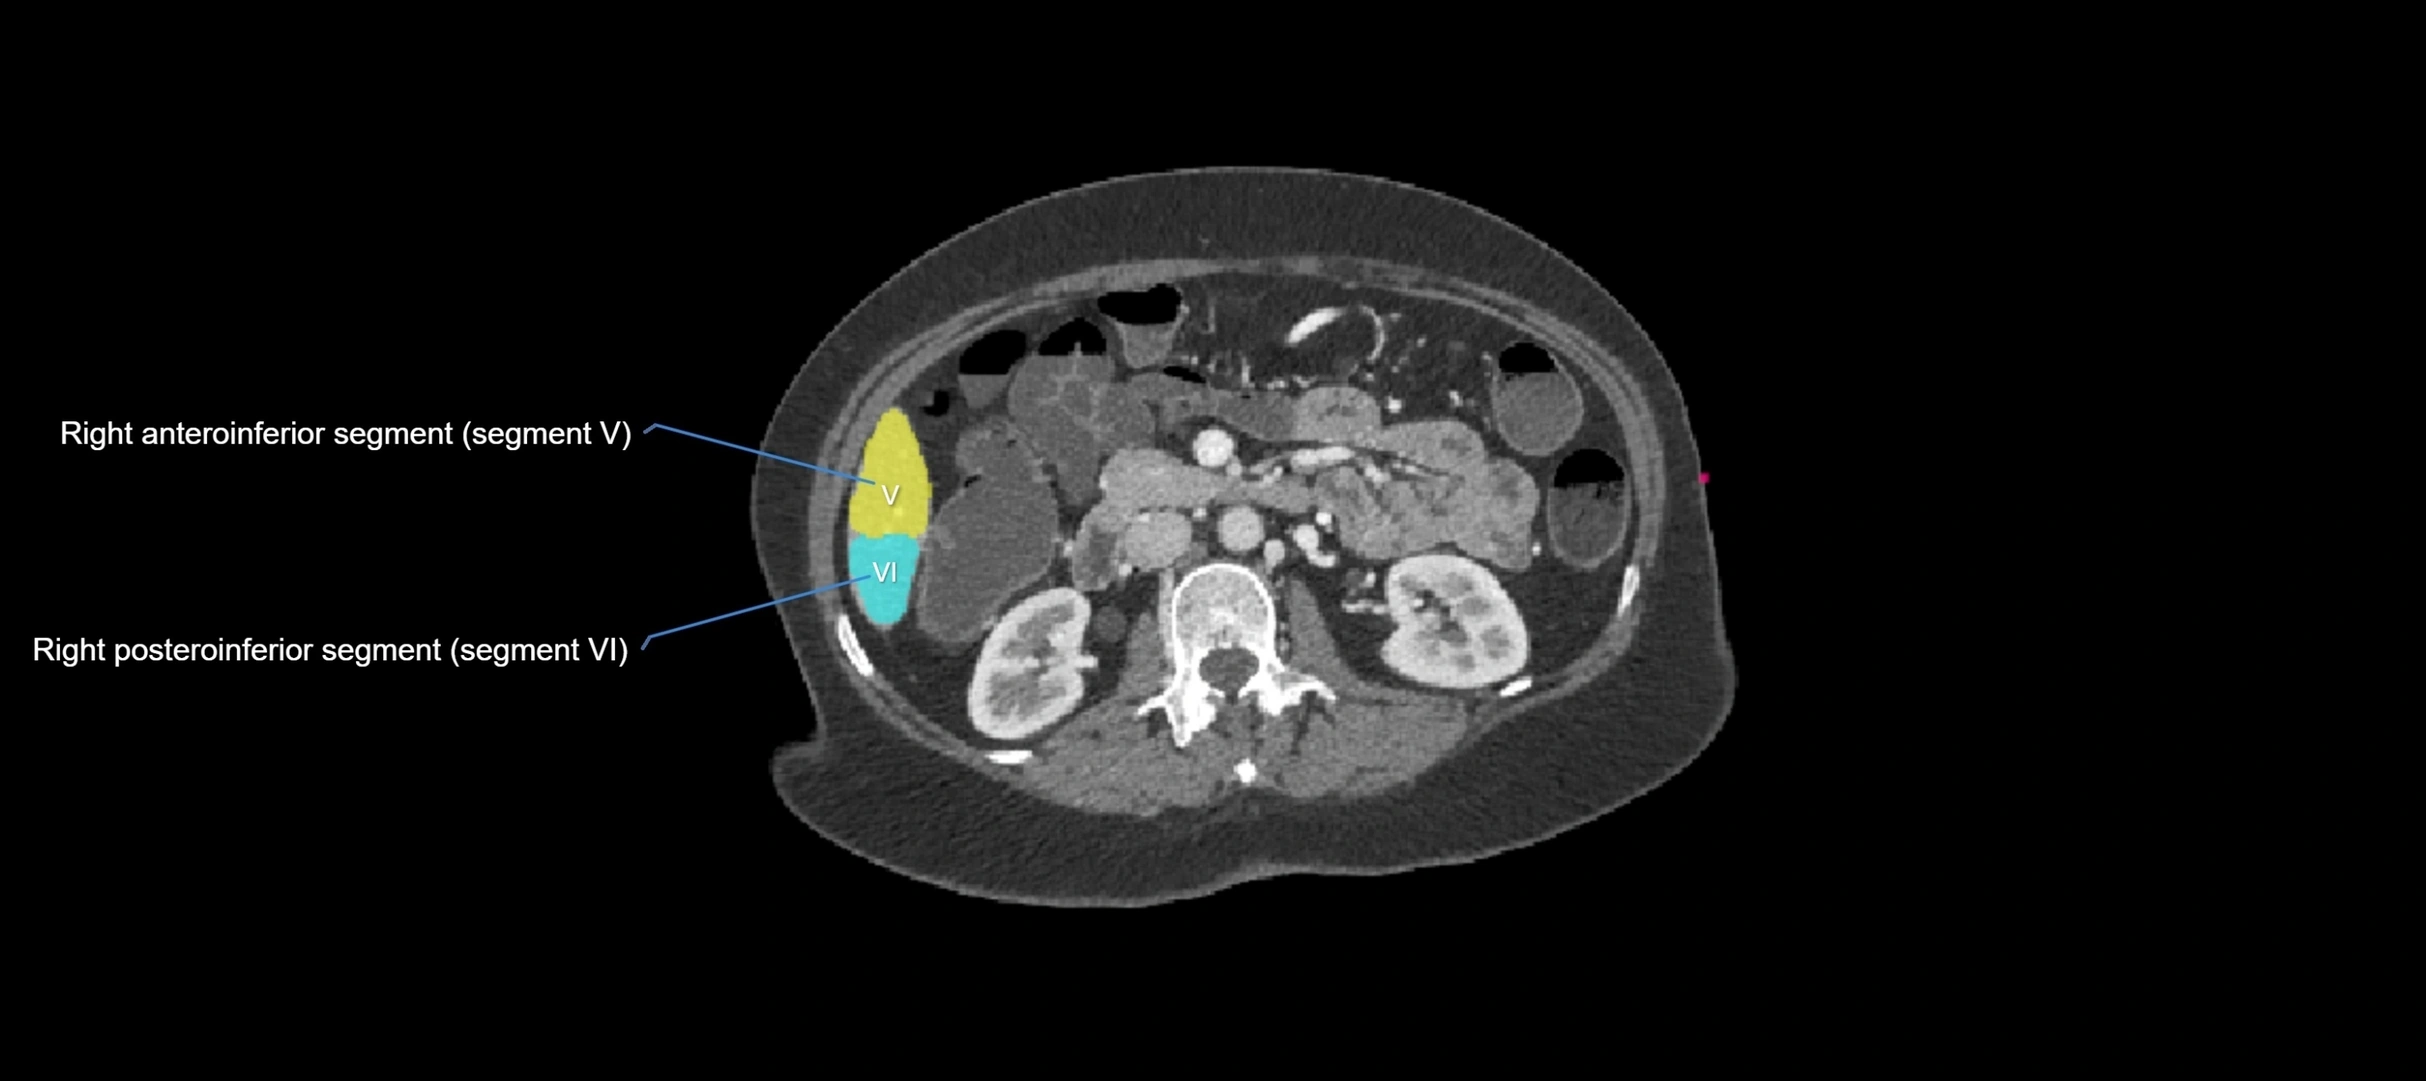

CT Image

image